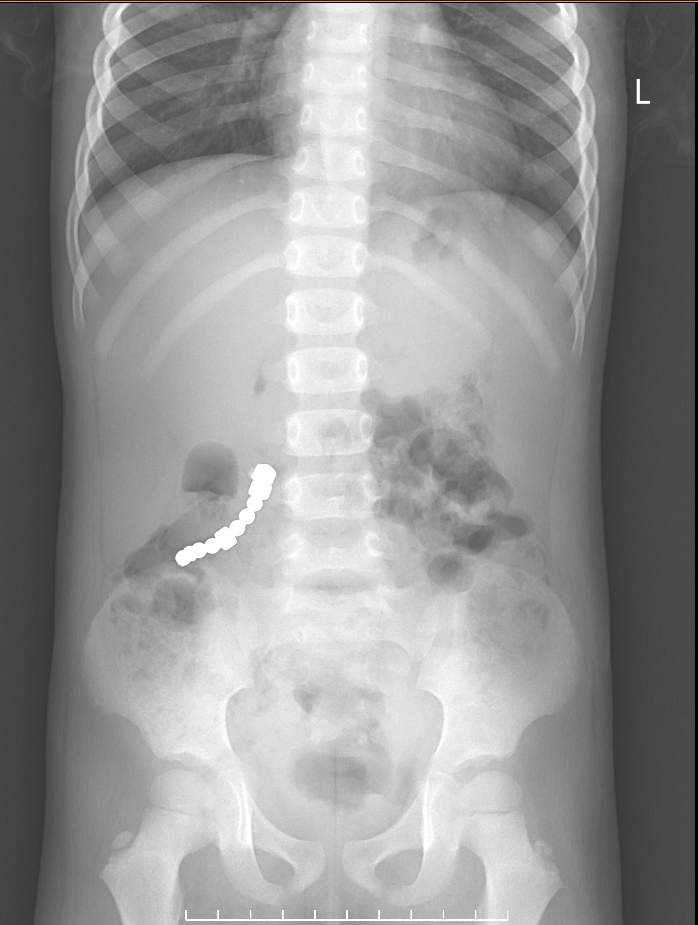

Theo lời kể của gia đình, bé trai có biểu hiện đau bụng liên tục vùng quanh rốn sau khi nuốt nam châm. Ngay lập tức, bé được đưa đến Viện Sản Nhi Bắc Ninh để thăm khám. Kết quả chụp X-quang cho thấy có dị vật cản quang tại ruột non, nghi ngờ là nam châm.

Sau khi khai thác bệnh sử và tiến hành các xét nghiệm cần thiết, các bác sĩ chẩn đoán bé bị dị vật nam châm trong hệ tiêu hóa. Tình trạng của bé vô cùng nguy hiểm bởi nếu không được can thiệp kịp thời, hai thanh nam châm có thể kẹt lại với nhau ở các vị trí khác nhau của ruột, gây tắc ruột, thậm chí là thủng ruột, ảnh hưởng nghiêm trọng đến sức khỏe của bé.

Nhận định đây là trường hợp khẩn cấp, các bác sĩ đã nhanh chóng tiến hành phẫu thuật để loại bỏ dị vật ra khỏi cơ thể bé. Sau ca phẫu thuật thành công, bé được theo dõi và điều trị tích cực trong 7 ngày. Rất may mắn, sức khỏe của bé đã dần ổn định và bé được xuất viện trong niềm vui mừng vô bờ bến của gia đình.